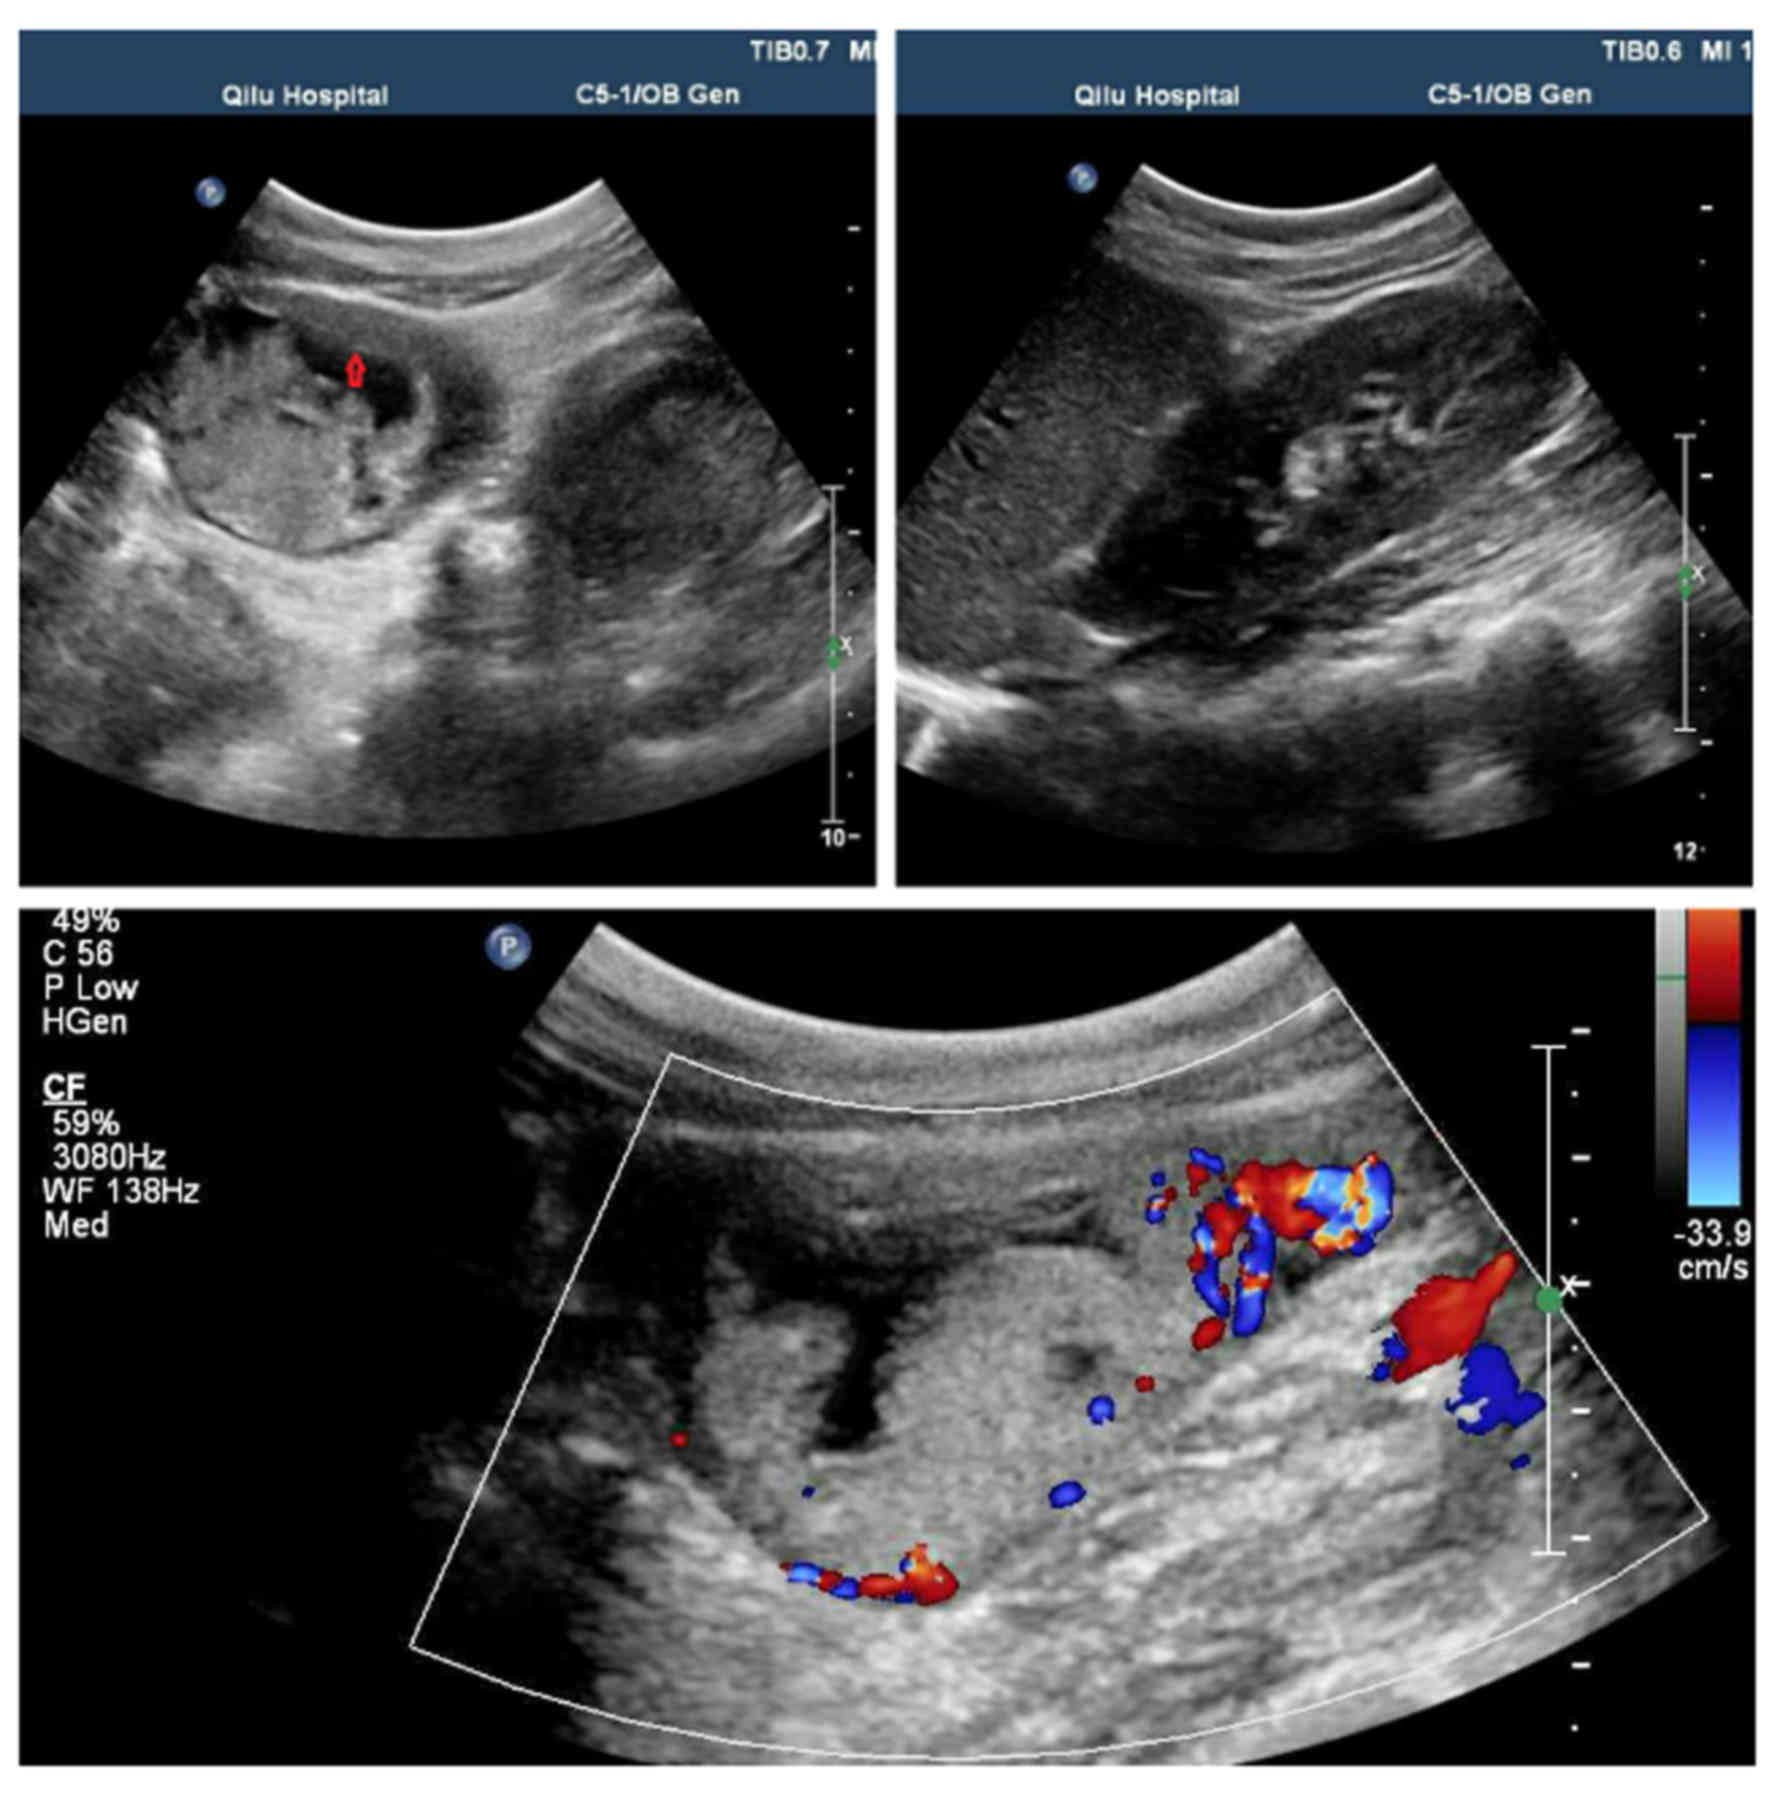

ultrasound and the pelvic magnetic resonance imaging (MRI) scan are

reported in Figs. 1 and 2. The ultrasound illustrates a suspicious

gestational trophoblastic disease in the rudimentary uterine horn,

with a rich blood flow signal at the right side of the uterus.